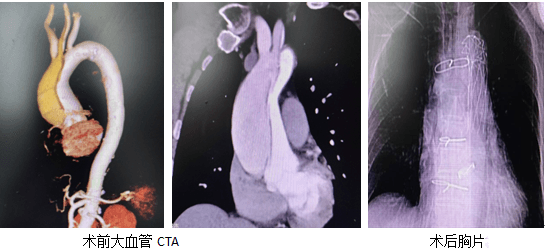

急查床旁超聲檢查驗證了她的推斷,之后立即前往CT室行大血管CTA后明確了診斷,主動脈夾層動脈瘤A型(II型),左頸總動脈撕裂嚴重,所以這就完全能驗證了他的頭暈癥狀,并且夾層撕裂至兩側冠脈口附近,破口多處。